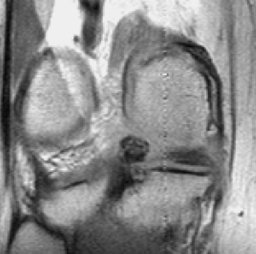

In this case arrows to highlight the abnormality are displayed only on user's request after the user clicks on description or diagnosis.

Case 4

5976.jpg (16246 bytes)6040.jpg (13715 bytes)